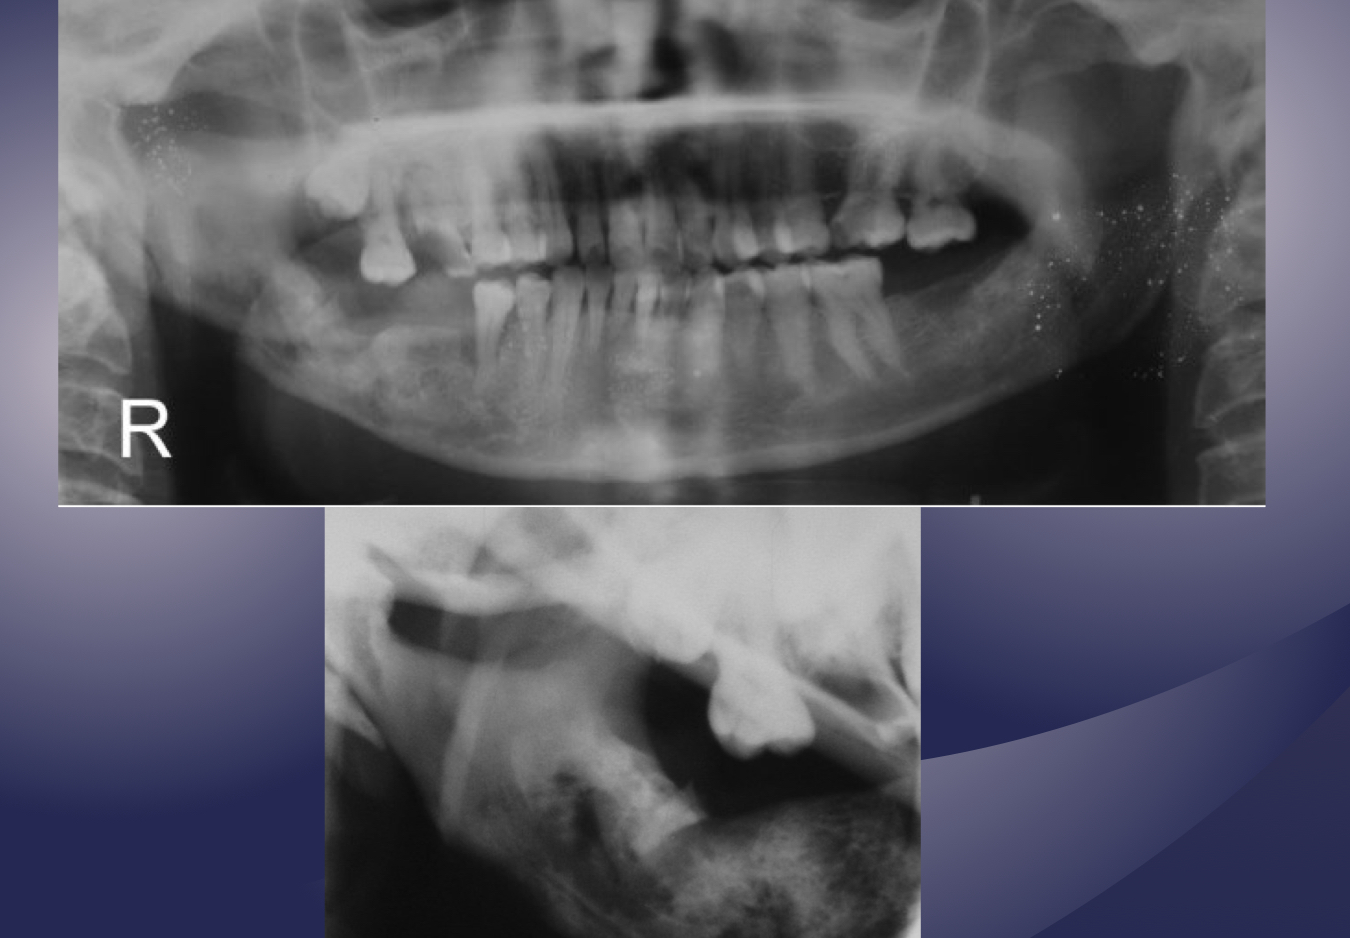

which osteomyelitis phase?

internal structure:

sequestration, sinus tract or fracture

acute

white and black arrow

which imaging is method of choice for seeing internal structure (sequestrea) of acute osteomyelitis?

CT/CBCT

what’s going on here?

what is going on here?

pathological fracture, facture on a compromised boone